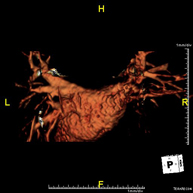

Prova diagnòstica no invasiva que consisteix en l'obtenció d'imatges d'alta definició anatòmica de les artèries cerebrals mitjançant l'ús d'un camp electromagnètic i ones de ràdio (amb un emissor i un receptor). No utilitza radiació ionitzant. En la majoria dels casos és necessari l'ús de contrast paramagnètic (Gadolini). Permet un estudi angiogràfic no invasiu gràcies a la injecció de Gadolini amb posterior reconstrucció en 2D i 3D, gràcies a estacions de treball especialitzades. Indicacions: malformacions vasculars, aneurismes d'artèries cerebrals i arteriosclerosi. - Angio-RM de Troncs supraaòrtics

Prova diagnòstica no invasiva que consisteix en l'obtenció d'imatges d'alta definició anatòmica de les artèries cerebrals mitjançant l'ús d'un camp electromagnètic i ones de ràdio (com un emissor i un receptor). No utilitza radiació ionitzant. En la majoria dels casos és necessari l'us de contrast paramagnètic (Gadolino). Permet un estudi angiogràfic no invasiu gràcies a la injecció de Gadolino amb una reconstrucció posterior en 2D i 3D gràcies a estacions de treball especialitzades. Indicacions: malformacions vasculars, aneurismes d'artèries cerebrals, arteriosclerosi. - Angio-RM de troncs supraaòrtics

Prova diagnòstica no invasiva que consisteix en l'obtenció d'imatges d'alta definició anatòmica de les artèries caròtides i vertrebrals a nivell de coll mitjançant l'ús d'un camp electromagnètic i ones de ràdio (com un emissor i un receptor). No utilitza radiació ionitzant. En la majoria dels casos és necessari l'us de contrast paramagnètic (Gadolino). Permet un estudi angiogràfic no invasiu gràcies a la injecció de Gadolino amb una reconstrucció posterior en 2D i 3D gràcies a estacions de treball especialitzades. Indicacions: problemes circulatoris cerebrals, síncope. - RM espectroscòpia cerebral